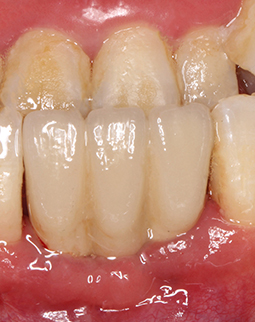

前几天回医院复诊检查和取模了发现我的种植体愈合挺好,今天过去准备把临时牙戴上,赶紧把这个空洞给补了,不然太尴尬了,戴牙冠之后医生给我把牙冠重新打磨了一下,说是要调整咬合,还要我模拟了下日常的咀嚼动作。哈哈哈,说件搞笑的事吧,我看见医生桌子上有个苹果,当即抓过来啃了一口,哈哈哈哈,这苹果太甜太好吃了,但医生还是建议我,先不要去吃硬物,等种植体再生长牢固一些,到时候想吃啥就吃啥。

到今天为止,我算是马上就有牙了。回想刚种牙那天,整个过程一点都没有痛觉,感觉自己就是在牙椅上睡了一觉,醒来后牙齿就长出来了,一切感觉是在做梦一样,非常棒的技术,戴上临时牙之后,可以正常的工作,也可以出席各类公开的活动,基本上解决了之前很多的麻烦,但还是不能吃太硬的东西,不太敢吃,医生跟我说“伤筋动骨一百天”,现在牙齿是戴上了,但是临时的,最主要是种植体还需要时间才能和我的牙床“相亲相爱”,接下来我就准备注意护理,让种植体早日和我的牙槽骨融为一体。